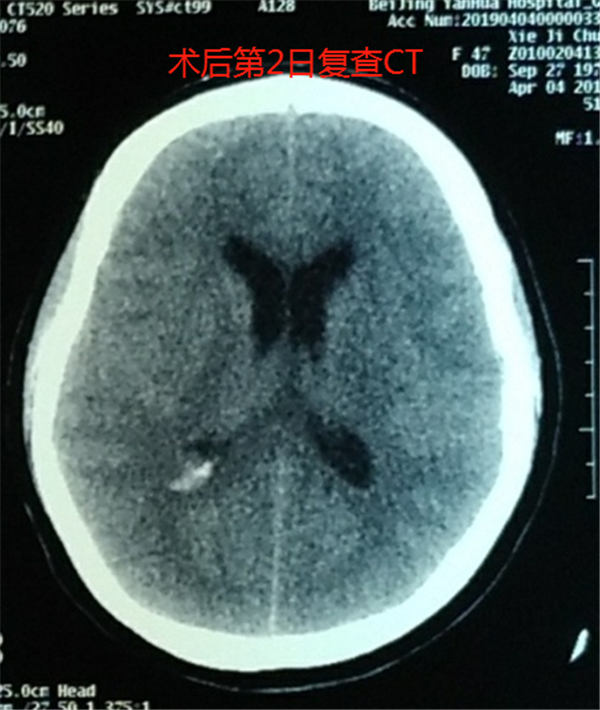

燕化医院神经外科经头颅CT检查发现,患者蛛网膜下腔出血,考虑脑动脉瘤破裂引起出血,遂给予止血等对症治疗,考虑病情较重,便紧急安排入院,以寻求进一步的治疗。

后经进一步的检查分析,医生在她的头颅CT平扫片子上发现了症结所在——在右侧颈内动脉及颈椎动脉均有可疑动脉瘤。

考虑到手术难度较大,4月3日,神经外科团队化身“拆弹部队”,用2小时的时间为谢女士实施了介入栓塞术,术中给予支架辅助下栓塞动脉瘤,术后动脉瘤闭塞,PICA动脉通畅,成功地将动脉瘤从脑血管中隔离出去。术后血管造影显示,动脉瘤已被弹簧圈填满,附近血管血流通畅。